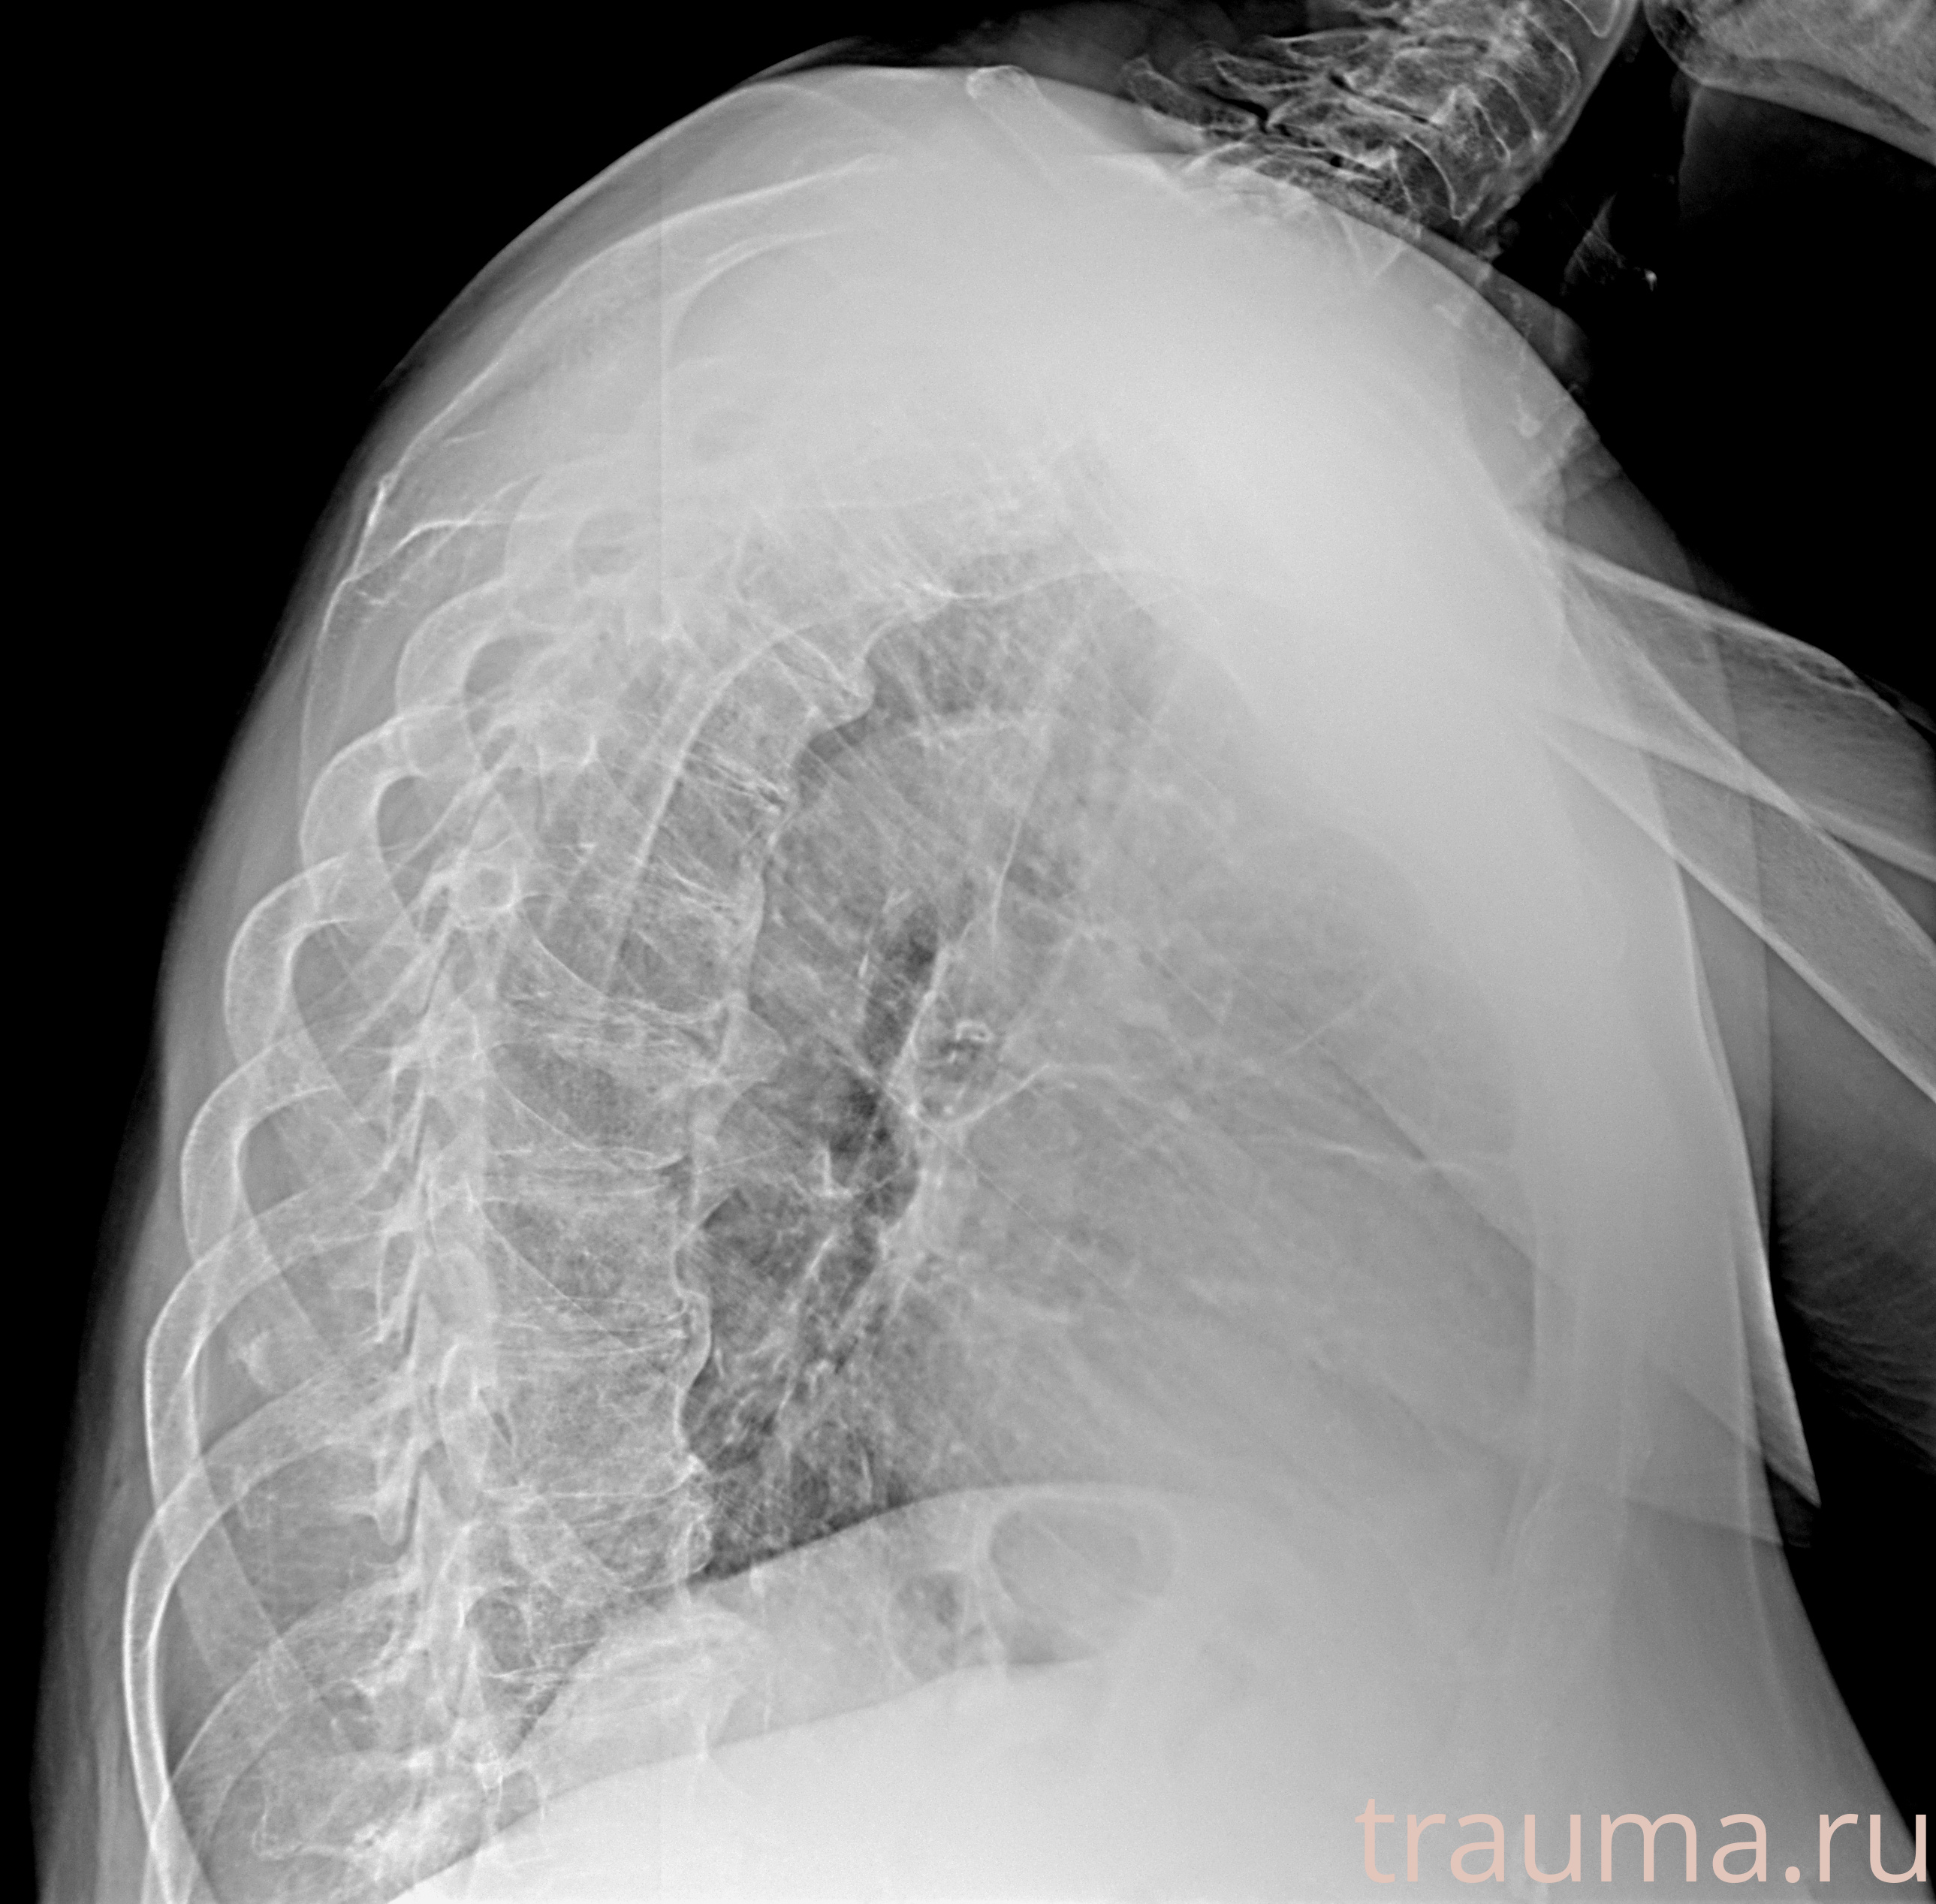

Рентген на дому: по вашему адресу приезжает врач-рентгенолог, травматолог-ортопед с мобильным рентгеновским аппаратом, проводит диагностику травмы или заболевания, делает необходимые рентгенограммы, дает рекомендации по дальнейшему лечению. Получить качественные снимки в домашних условиях возможно благодаря уникальной методике, разработанной МосРентген Центром для института  Склифосовского

при переломе шейки бедра и пневмонии от компании МосРентген Центр - партнера Института имени Склифосовского